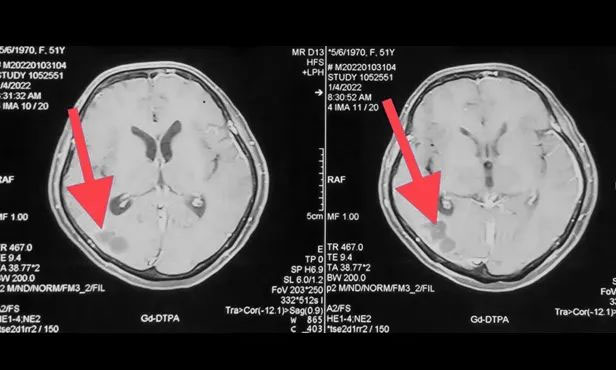

▲ 經(jīng)復(fù)查,病灶較前明顯縮小

按照腫瘤復(fù)查的標(biāo)準(zhǔn),復(fù)查影像顯示王女士顱內(nèi)病灶相較于來院時(shí)明顯縮小。家屬為此特意向陳琦主任致謝,并對(duì)醫(yī)院的治療和服務(wù)表達(dá)了充分肯定。